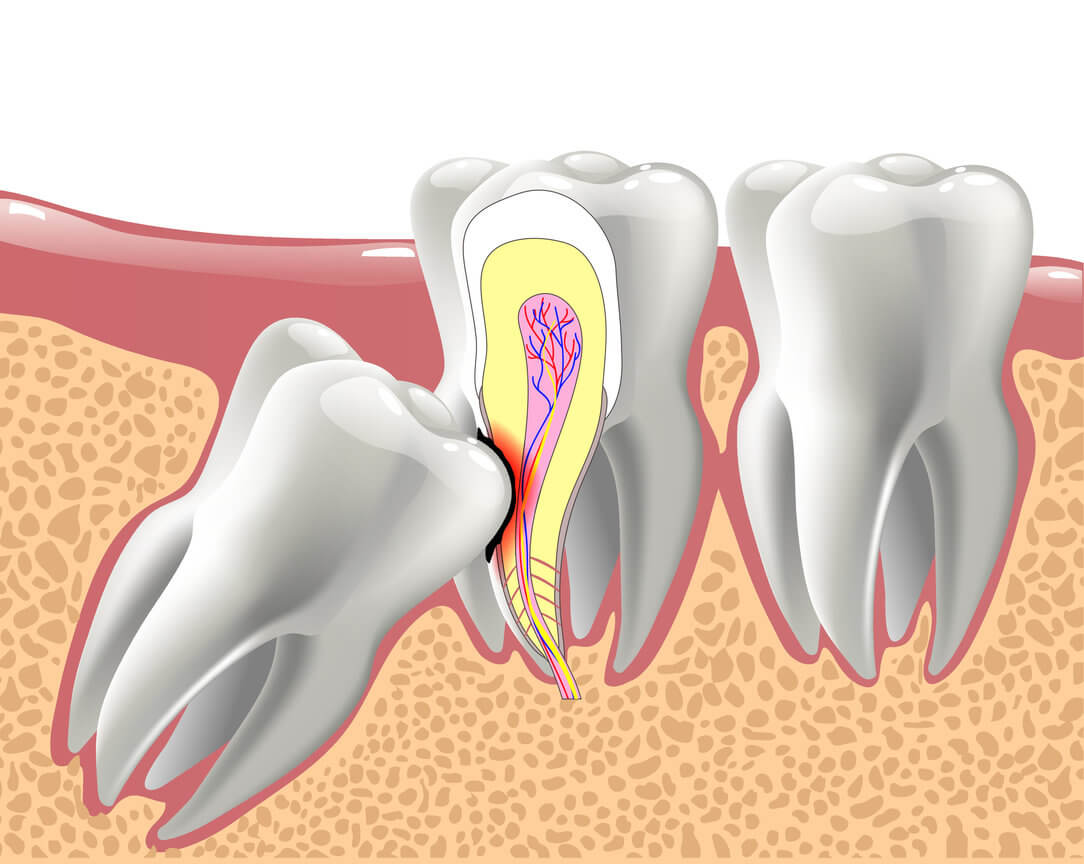

Wisdom tooth extraction is the removal of the four permanent molar teeth located at the top and bottom back corners of the mouth.we recommend that the wisdom teeth be removed early, preferably during the mid- to late teens, even if they haven’t begun to emerge from the gums yet.Call us for a free consultation at (281) 940-8940 or visit us At Edge Dental in Houston, TX.